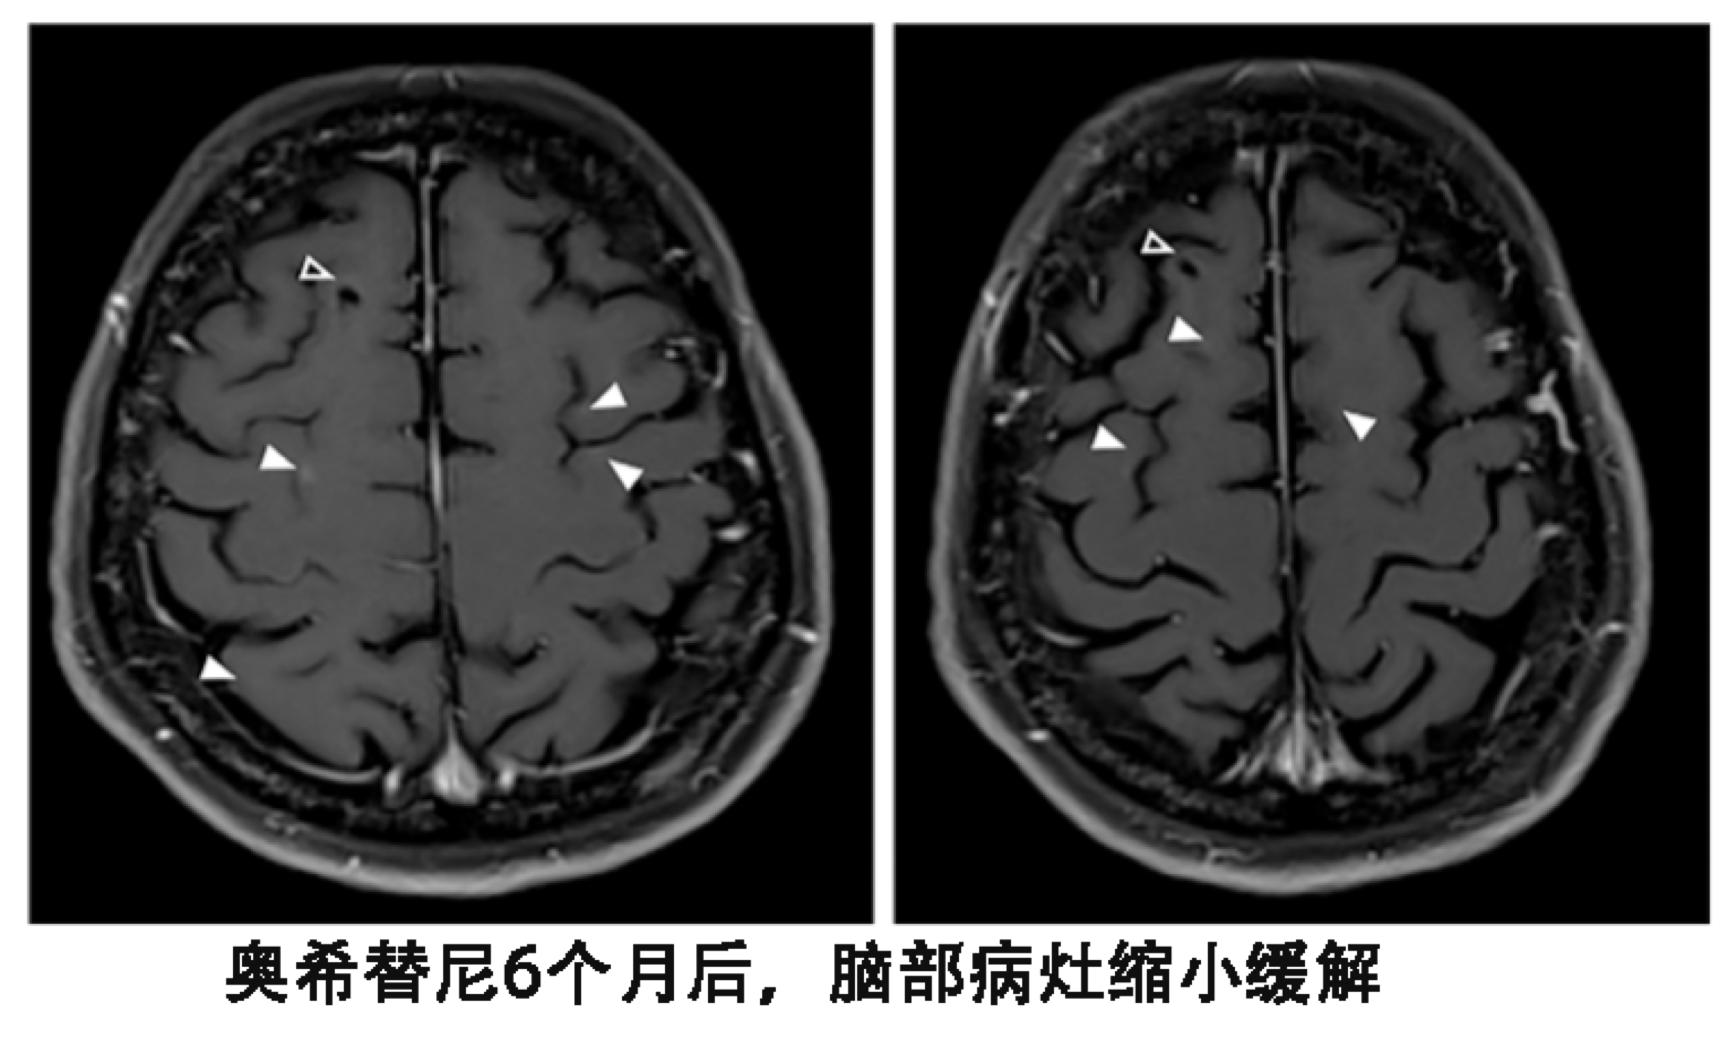

患者尽管血液基因检测T790M阴性,但是依然换用了第三代靶向药物泰瑞沙(AZD9291),每天的剂量为80毫克,结果出现了奇迹。患者的视觉双影没有了,脑脊液的细胞学检查也为阴性,脑部核磁显示脑皮质损伤有所改善。

尽管血液T790M检测为阴性,从换用9291之后,患者脑部病灶稳定了一年,另外脑外的病灶一直处于稳定状态。